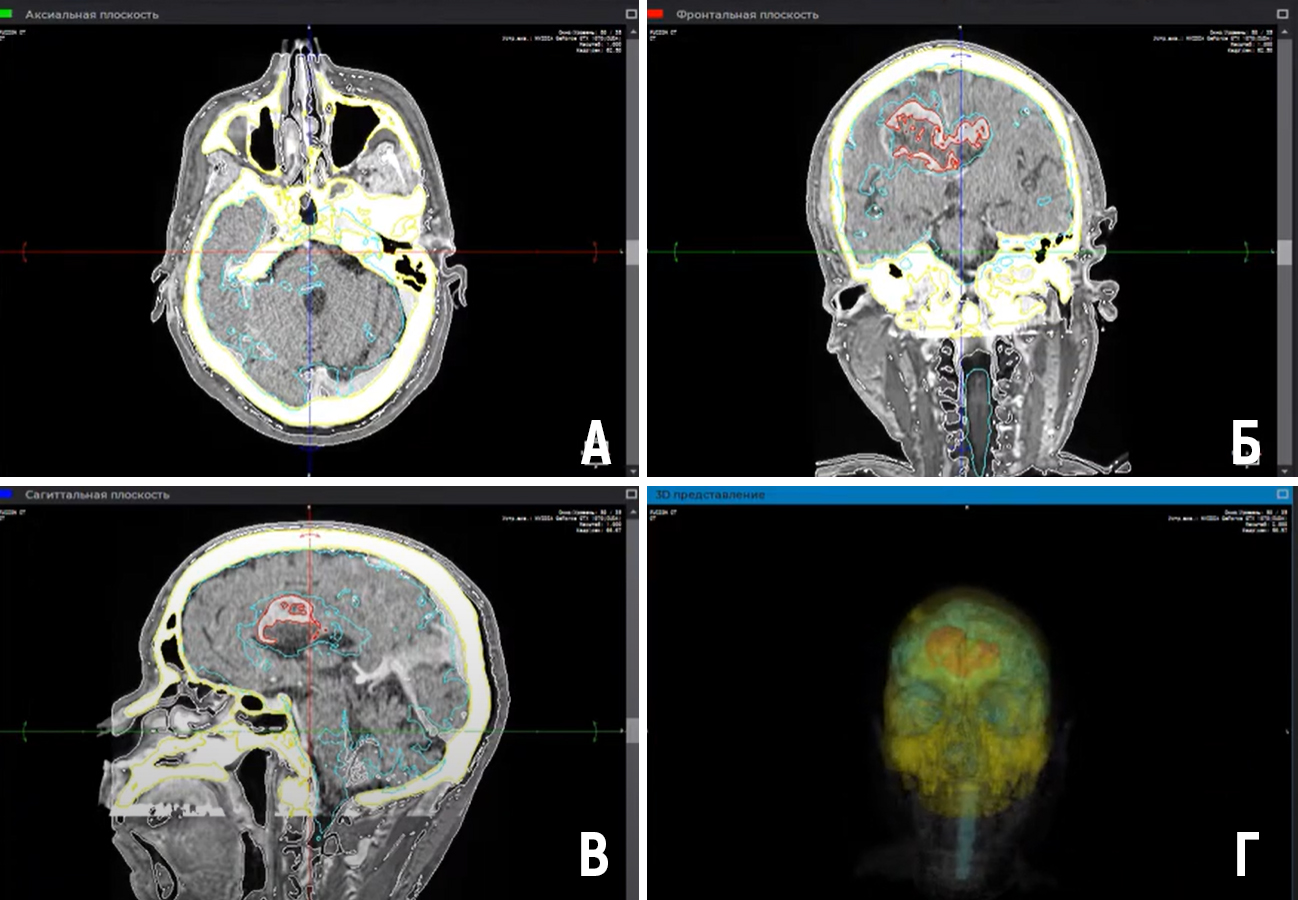

Цель – описание метода создания и опыта использования VR-библиотеки нейрохирургической интракраниальной патологии. Материалы и методы. Для создания 3D моделей использованы КТ и МРТ изображения. Сегментация производилась в программе Inobitec. Воспроизведение 3D моделей выполнялось в Blender с помощью VR-очков Oculus Quest 2. Результаты. Создана VR библиотека на основании данных 100 пациентов. Представлены 3 клинических наблюдения использования VR технологии. Заключение: VR-библиотека позволяет изучать индивидуальную анатомию пациентов, улучшать планирование операции.